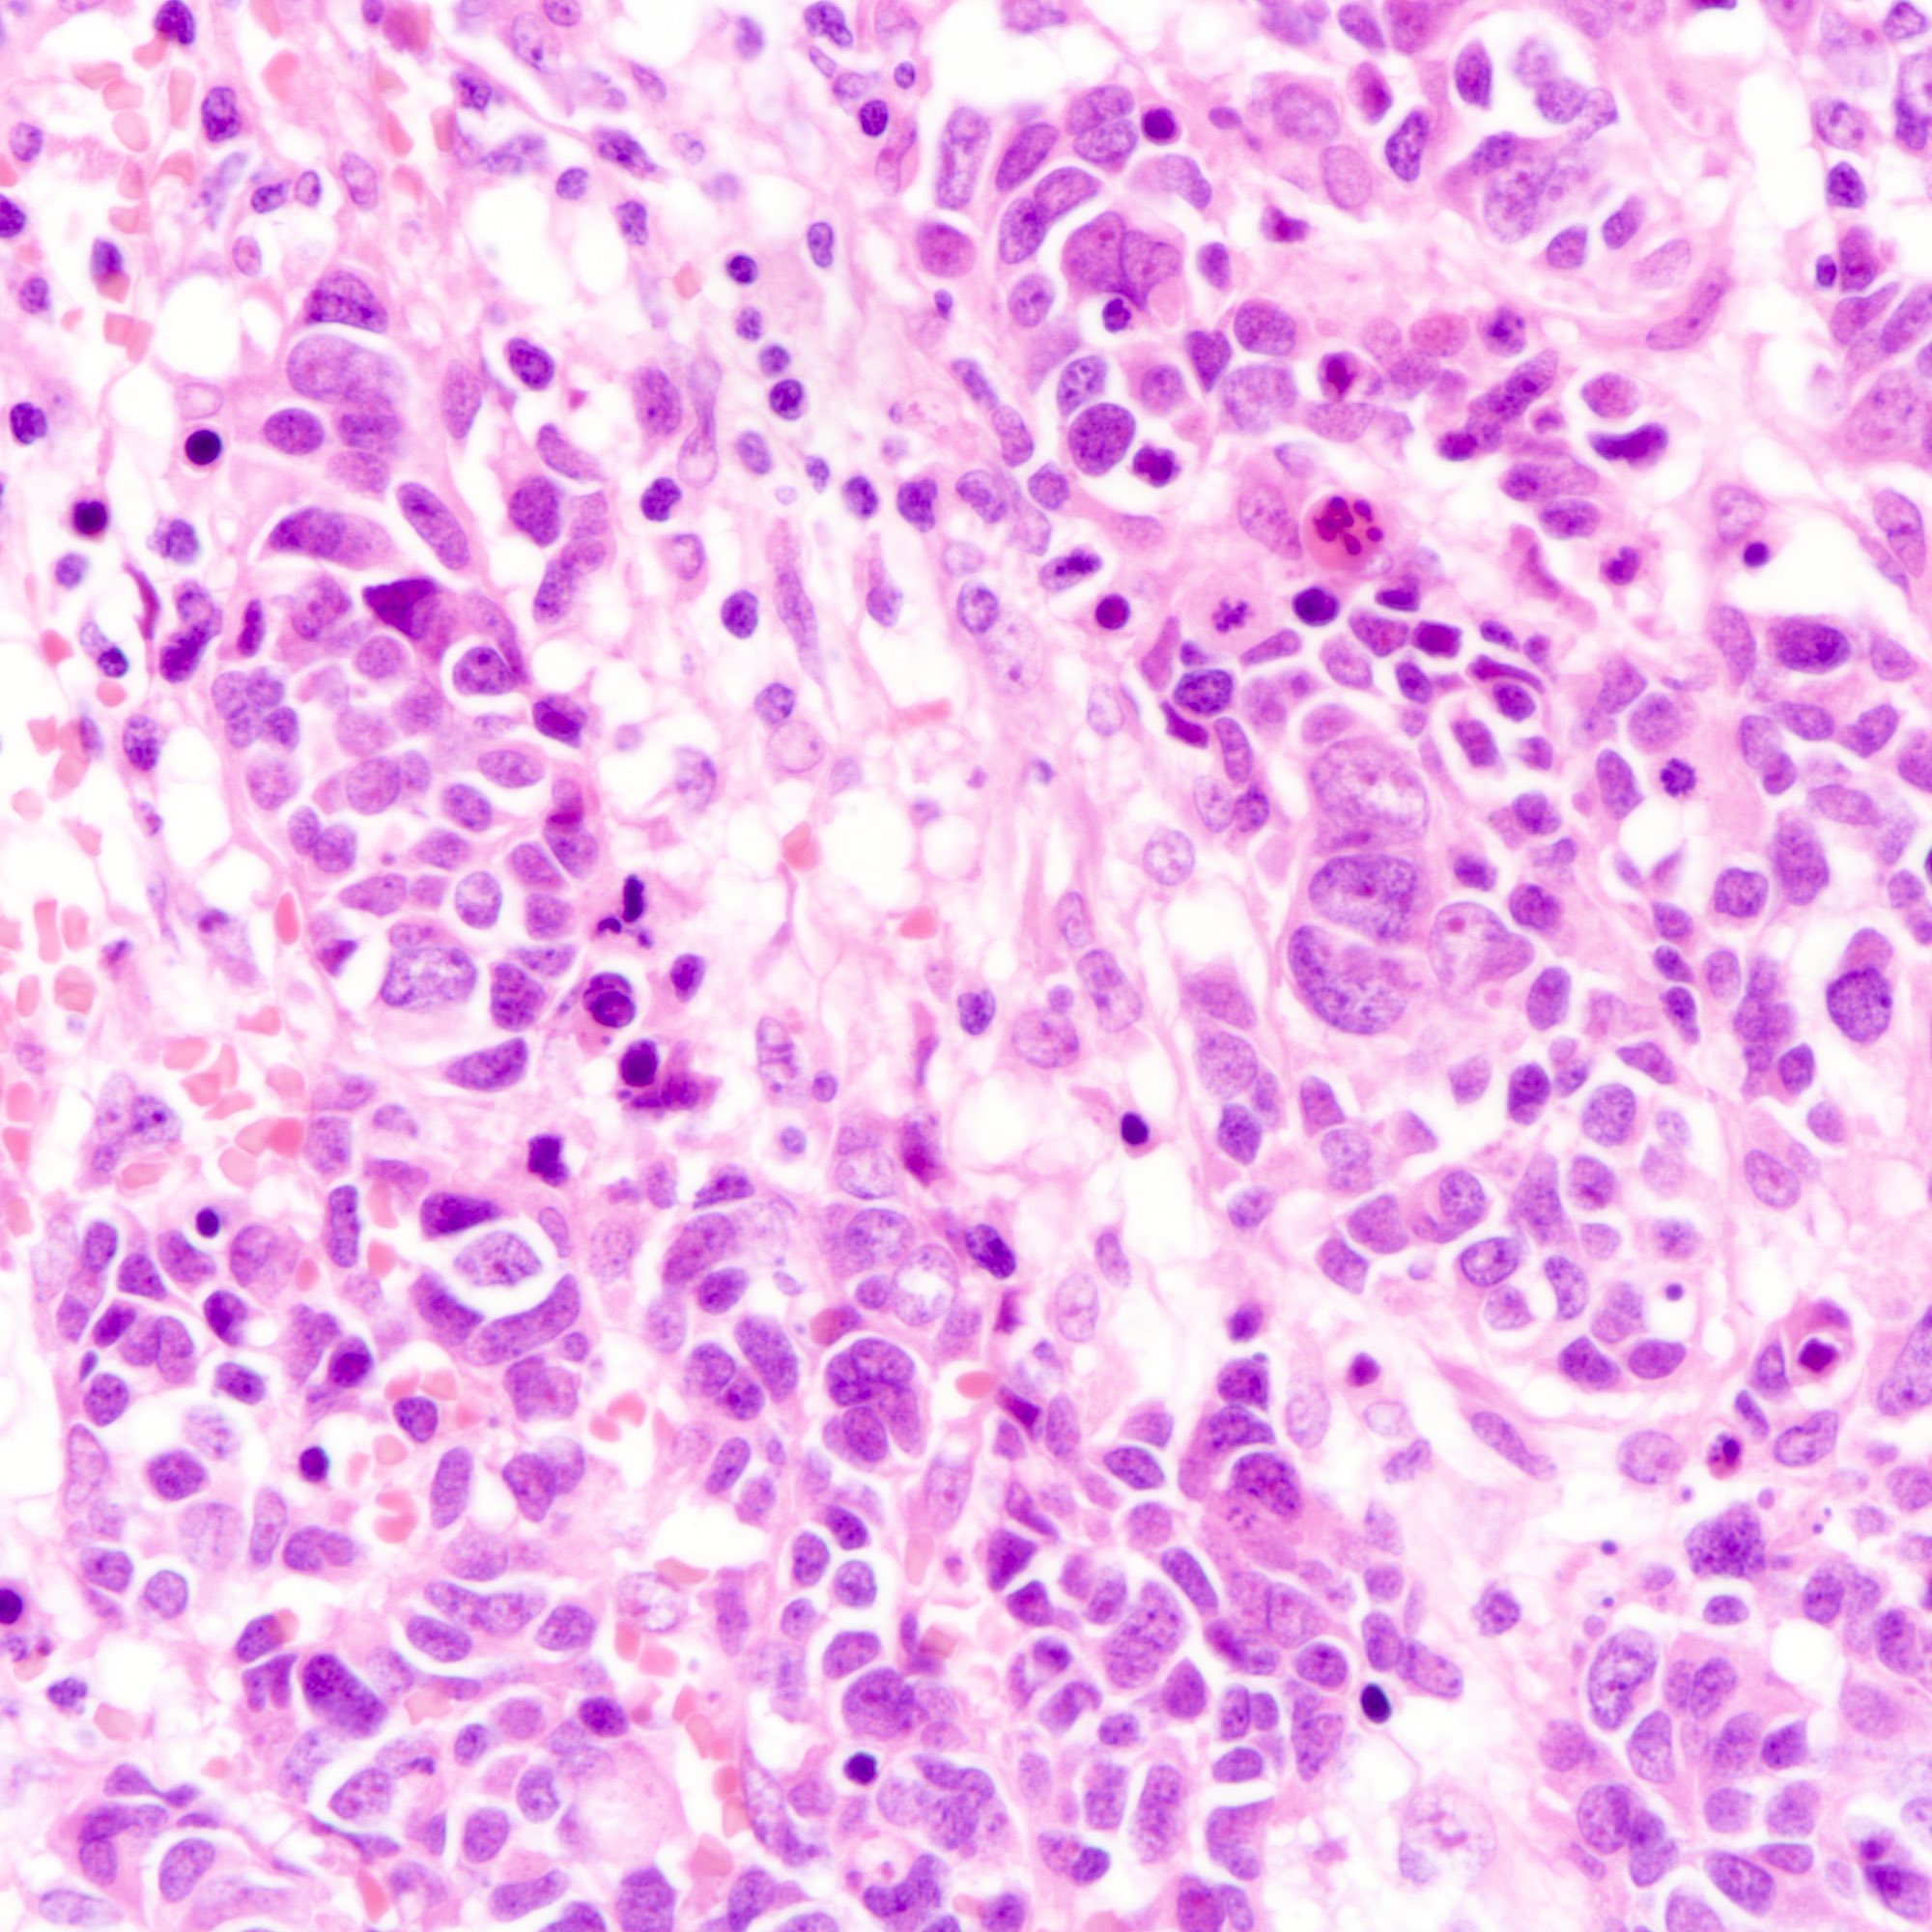

- Large cell carcinoma:

- High grade features (frequent necrosis, lymphovascular invasion and mitosis) similar to small cell carcinoma

- Tumor cells have a larger amount of cytoplasm

- Chromatin pattern coarse with occasional distinct nucleoli

- Neuroendocrine carcinomas of the breast histologically indistinguishable from their counterparts of other primaries

Microscopic (histologic) images

Contributed by Joshua J.X. Li, M.B.Ch.B., Gary M. Tse, M.B.B.S. and Kristen E. Muller D.O.

Large cell carcinoma

- Large cell carcinoma (see comment)

- Comment: Sections show breast tissue infiltrated by nests and sheets of tumor cells. The tumor cells possess enlarged nuclei with coarse chromatin pattern, distinct nucleoli and a moderate amount of cytoplasm. The mitotic count is at __ per 10 high power fields. The tumor measures __ in maximal dimension and is clear from (specify if < 1 cm __) / involves the resection margins.

- The tumor cells are diffusely positive for synaptophysin and focally positive for chromogranin.